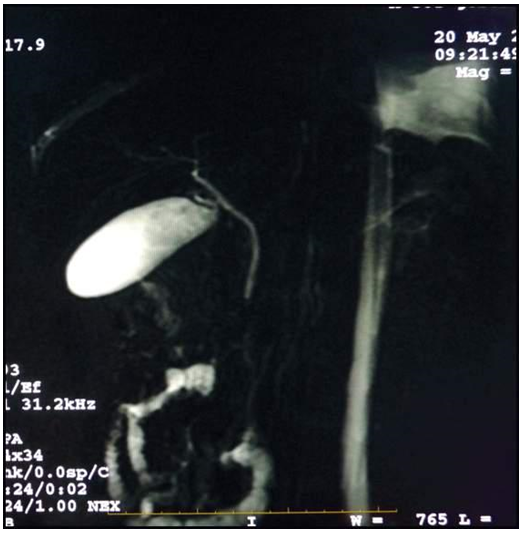

La colangioresonancia posterior, no evidenció parásitos residuales, ni obstrucción de la vía biliar (anexos, figura 4). Consecuentemente, la conducta terapéutica seguida fue iniciar antibioticoterapia utilizando Ampicilina/Sulbactam (por el alto riesgo de colangitis); así como antihelmíntico mediante albendazol.

Vesícula y vía biliar sin evidencia de obstrucción, ni parásitos residuales